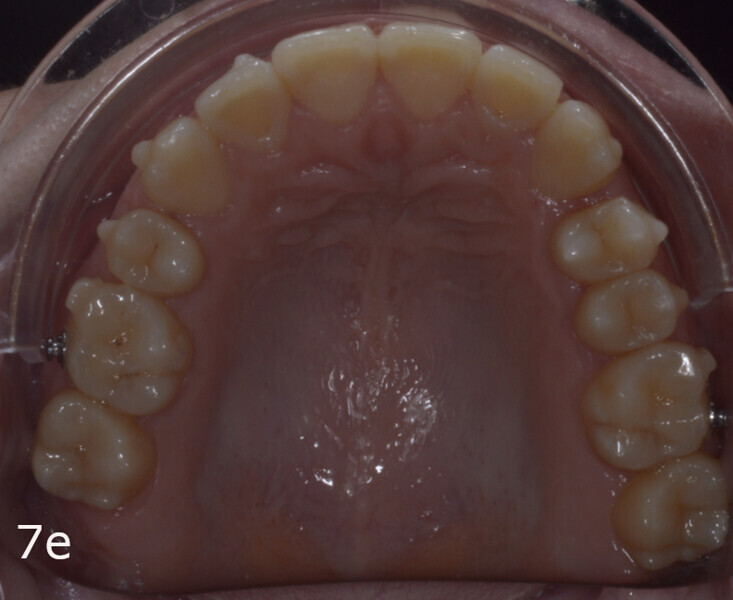

The 23-year-old dolichofacial female patient complained of not being able to chew properly. Facial examination showed a convex profile, an enlarged lower facial height, and a skeletal Class III malocclusion (Figs. 1–3). Intra-oral examination revealed an Angle Class III right subdivision malocclusion, anterior open bite, no overjet and a maxillary dental midline deviated about 3 mm to the right compared with the mandibular dental midline (Fig. 4). The panoramic radiograph confirmed previous extraction of the maxillary right first premolar and the presence of all four third molars (Figs. 5 & 6).

The treatment objectives included closing the anterior open bite, achieving a bilateral Angle Class I relationship and a proper overjet and overbite, correcting the midline discrepancies, and achieving a profile harmonisation. The treatment plan consisted of orthodontic camouflage treatment with asymmetric distalisation in three of the four quadrants using Invisalign aligners (Align Technology) and third molar extraction. The Invisalign Comprehensive package was chosen, and 63 pairs of aligners were used (Figs. 7–10). Each aligner was worn for 20 hours a day for one week each. The use of Class III elastics on both sides was indicated. Afterwards, ten refinement aligners were needed to improve the interdigitation on the right side (Figs. 11 & 12).

The total treatment time was 15 months. An Angle Class I relationship was established along with adequate anterior and canine guidance, establishing a functional occlusion. This not only ensures optimal masticatory function but also protects the teeth and the temporomandibular joint from excessive force. Maxillary and mandibular fixed retention were installed at the end of the treatment (Figs. 13–19).